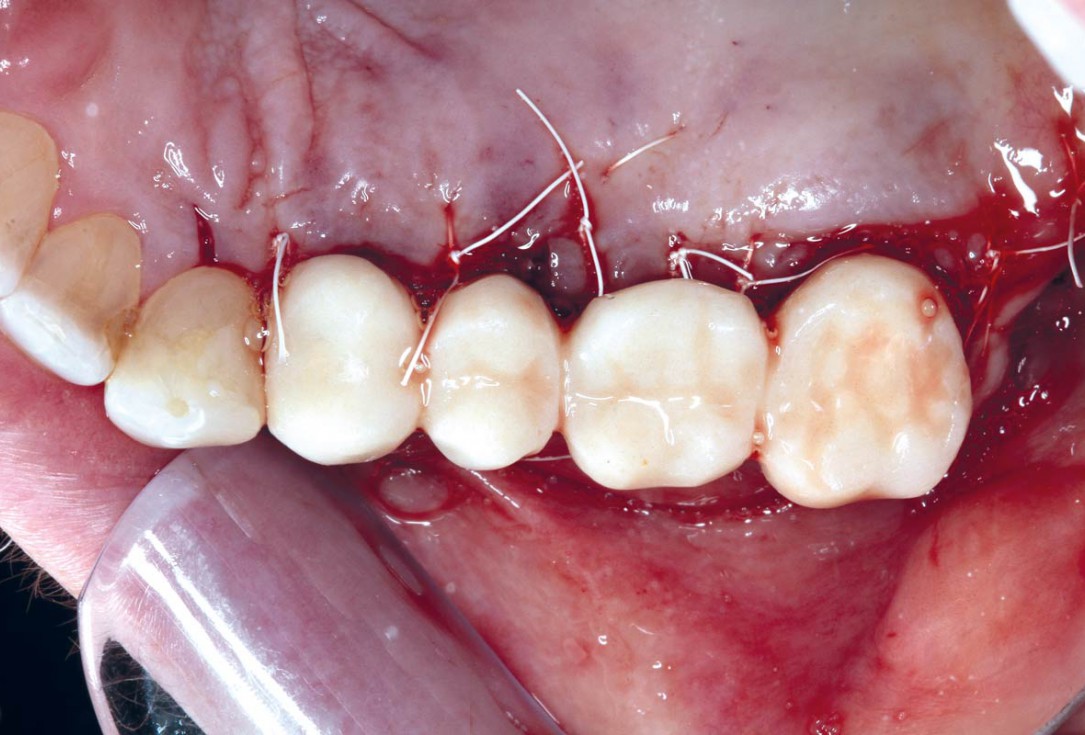

botiss-cerabone-permamem-maxgraft-mucoderm-horizontal-gbr-maghaireh

Initial situation - A young female 34 years old lost her front teeth in an surfing accident and she had a 5 unit bridge supported by her upper left lateral and right canine. The restoration failed and both supporting crowns have exposed and leaking margins.